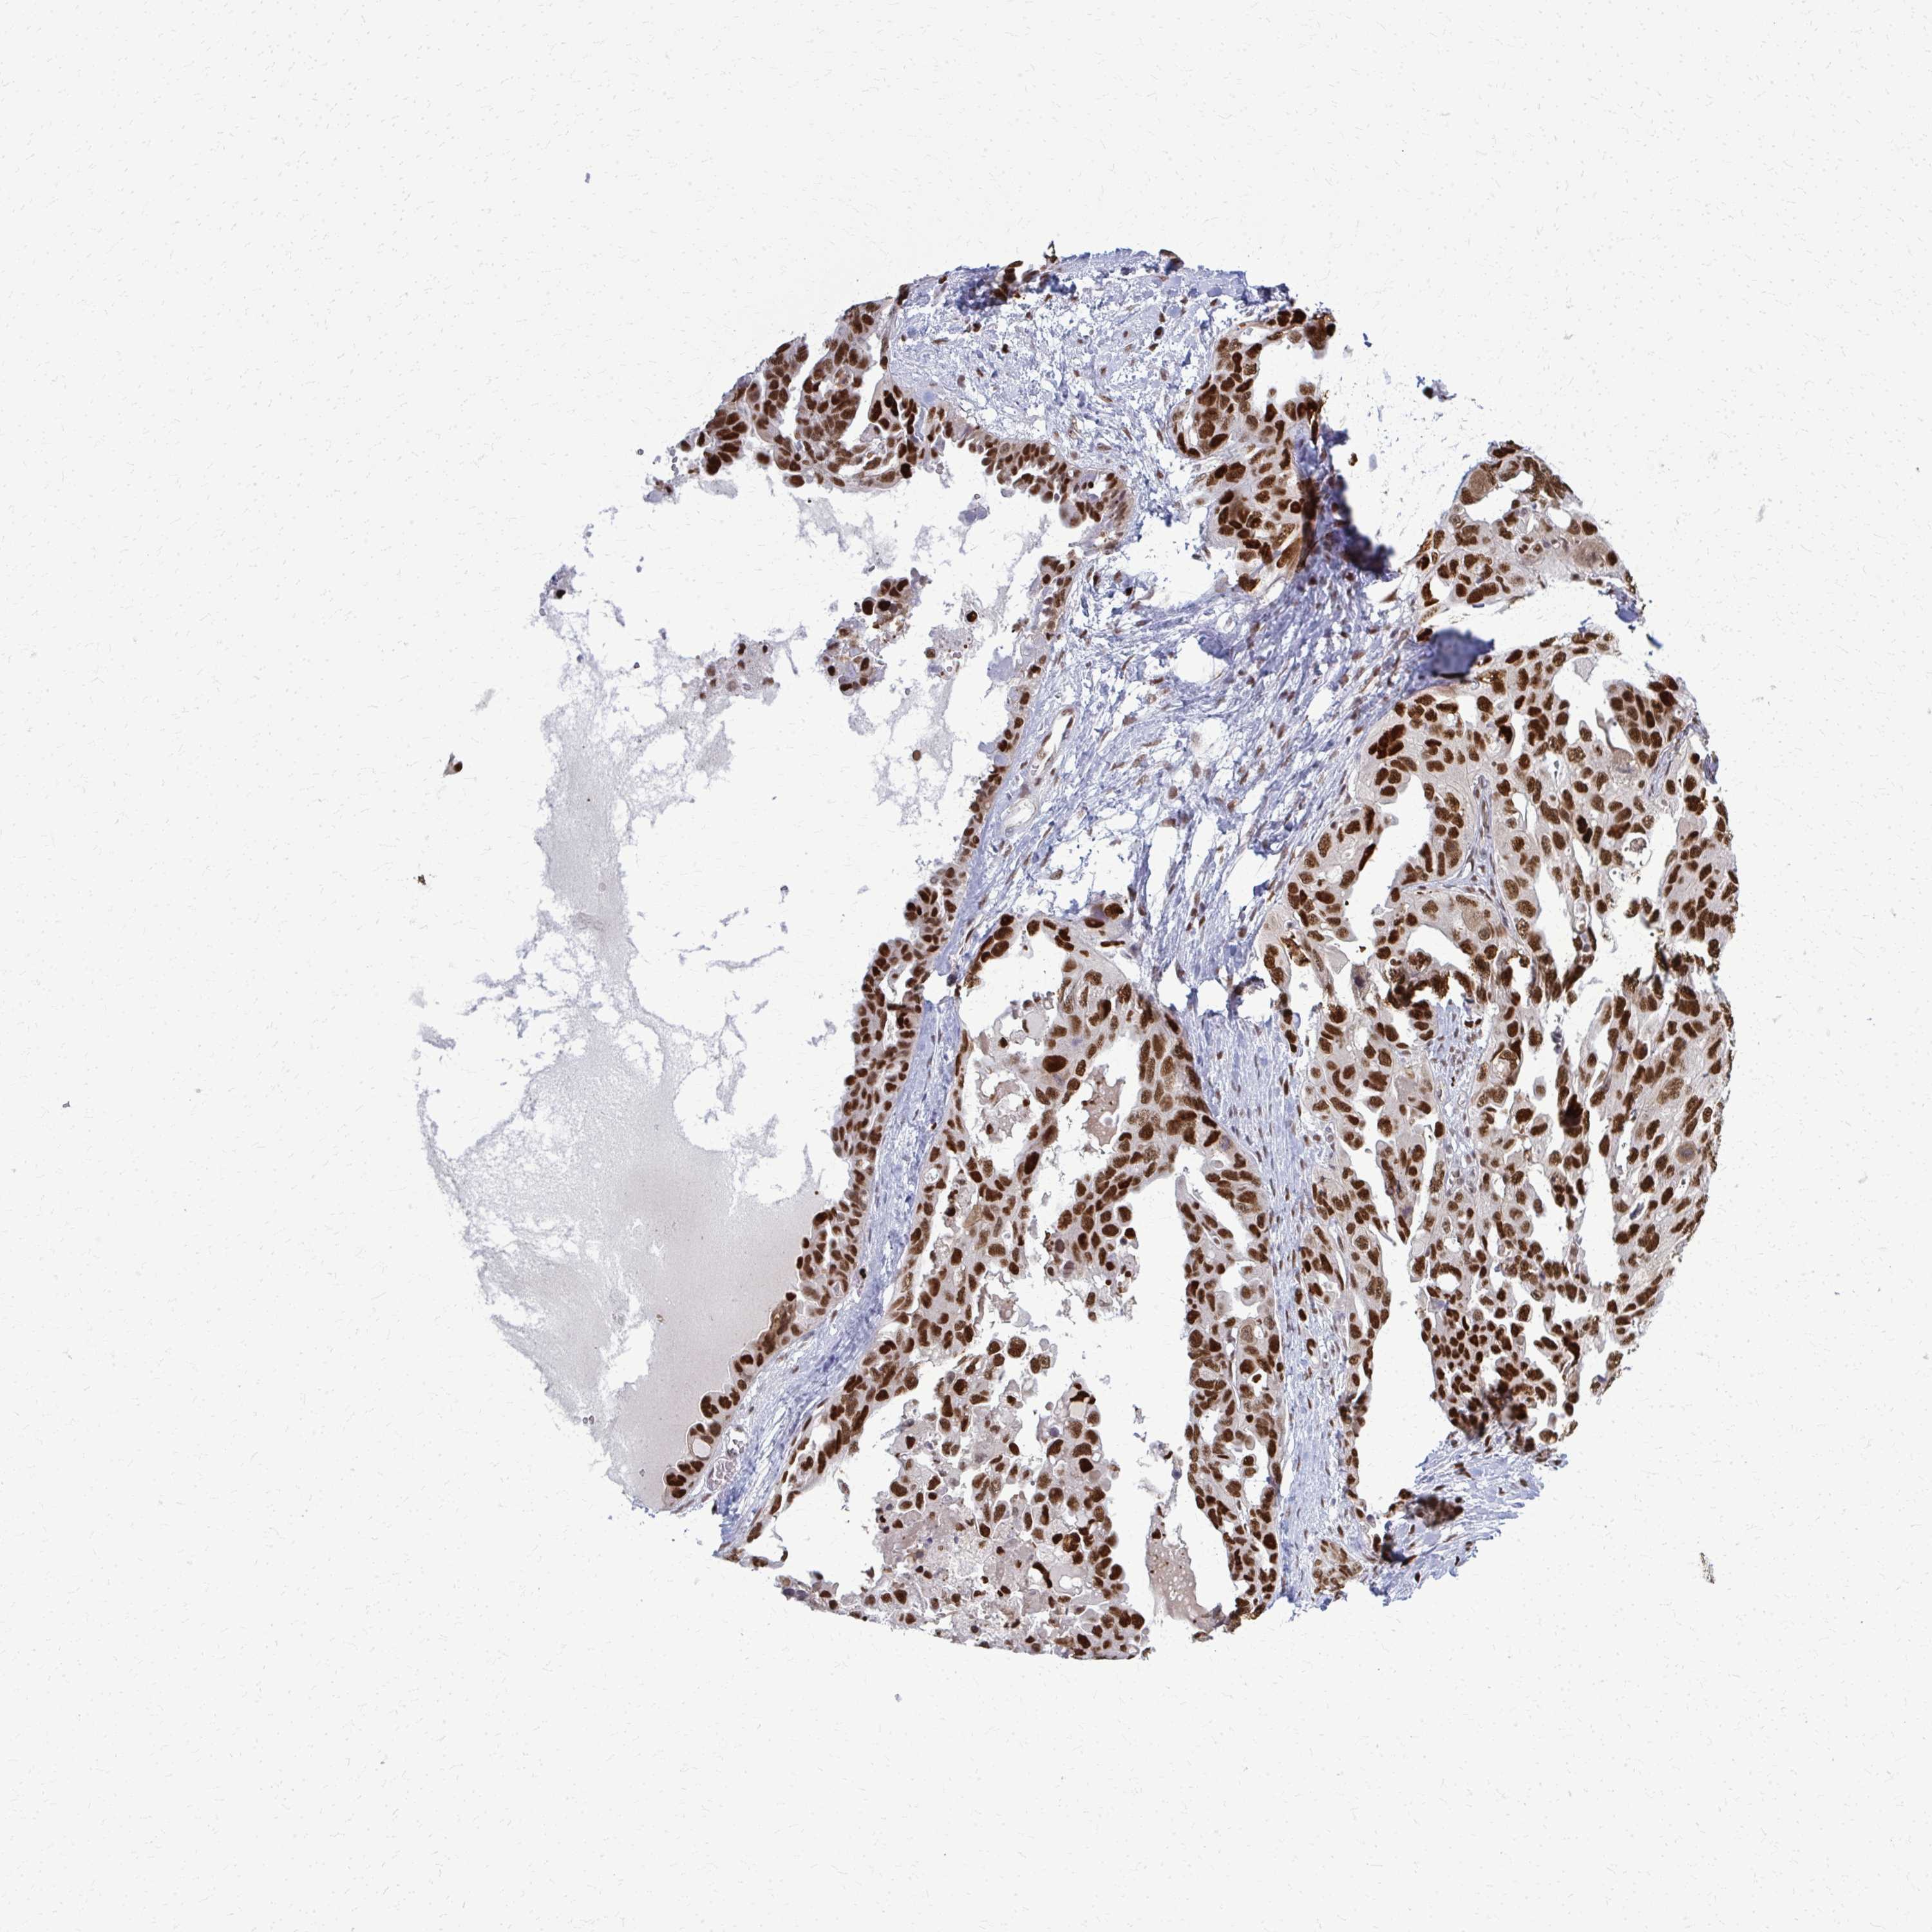

OVARIAN CANCER - Protein expressioni

A mouse-over function shows sample information and annotation data. Click on an image to view it in a full screen mode. Samples can be filtered based on level of antibody staining by selecting one or several of the following categories: high, medium, low and not detected. The assay and annotation is described here.

Note that samples used for immunohistochemistry by the Human Protein Atlas do not correspond to samples in the TCGA dataset.

Antibody stainingi

Antibody staining in the annotated cell types in the current human tissue is reported as not detected, low, medium, or high, based on conventional immunohistochemistry profiling in selected tissues. This score is based on the combination of the staining intensity and fraction of stained cells.

Each image is clickable and will lead to virtual microscopy that enables deeper exploration of all samples and also displays staining intensity scores, fraction scores and subcellular localization as well as patient and tissue information for each sample.

Antibody HPA059632

Staining

High

Medium

Low

Not detected

Intensity

Strong

Moderate

Weak

Negative

Quantity

>75%

75%-25%

<25%

None

Location

Nuclear

Cytoplasmic/membranous

Cytoplasmic/membranous,nuclear

Cystadenocarcinoma, serous, NOS

Carcinoma, NOS

Cystadenocarcinoma, mucinous, NOS

Carcinoma, endometroid